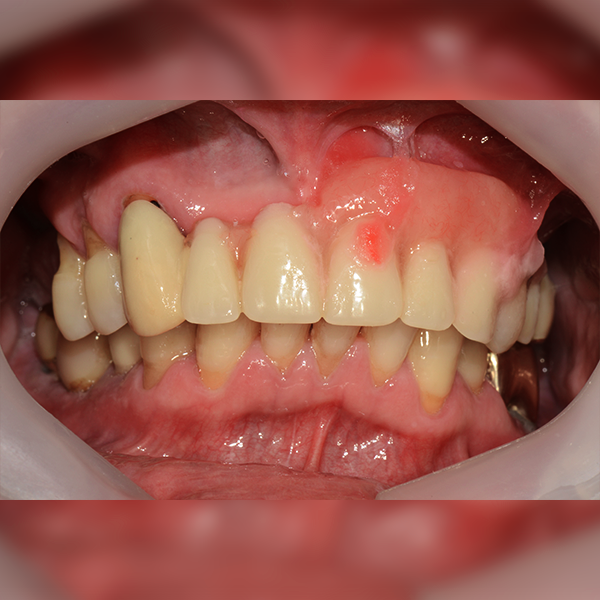

3. Trường hợp 205 Shim*Soo, 60 tuổi 2017-12-12 / 2018-11-22

Nha khoa One Day

Hàm dưới / Vùng răng hàm / Tối đa 3 cái / Ghép xương

Trường hợp 205 Shim*Soo, 60 tuổi 2017-12-12 / 2018-11-22